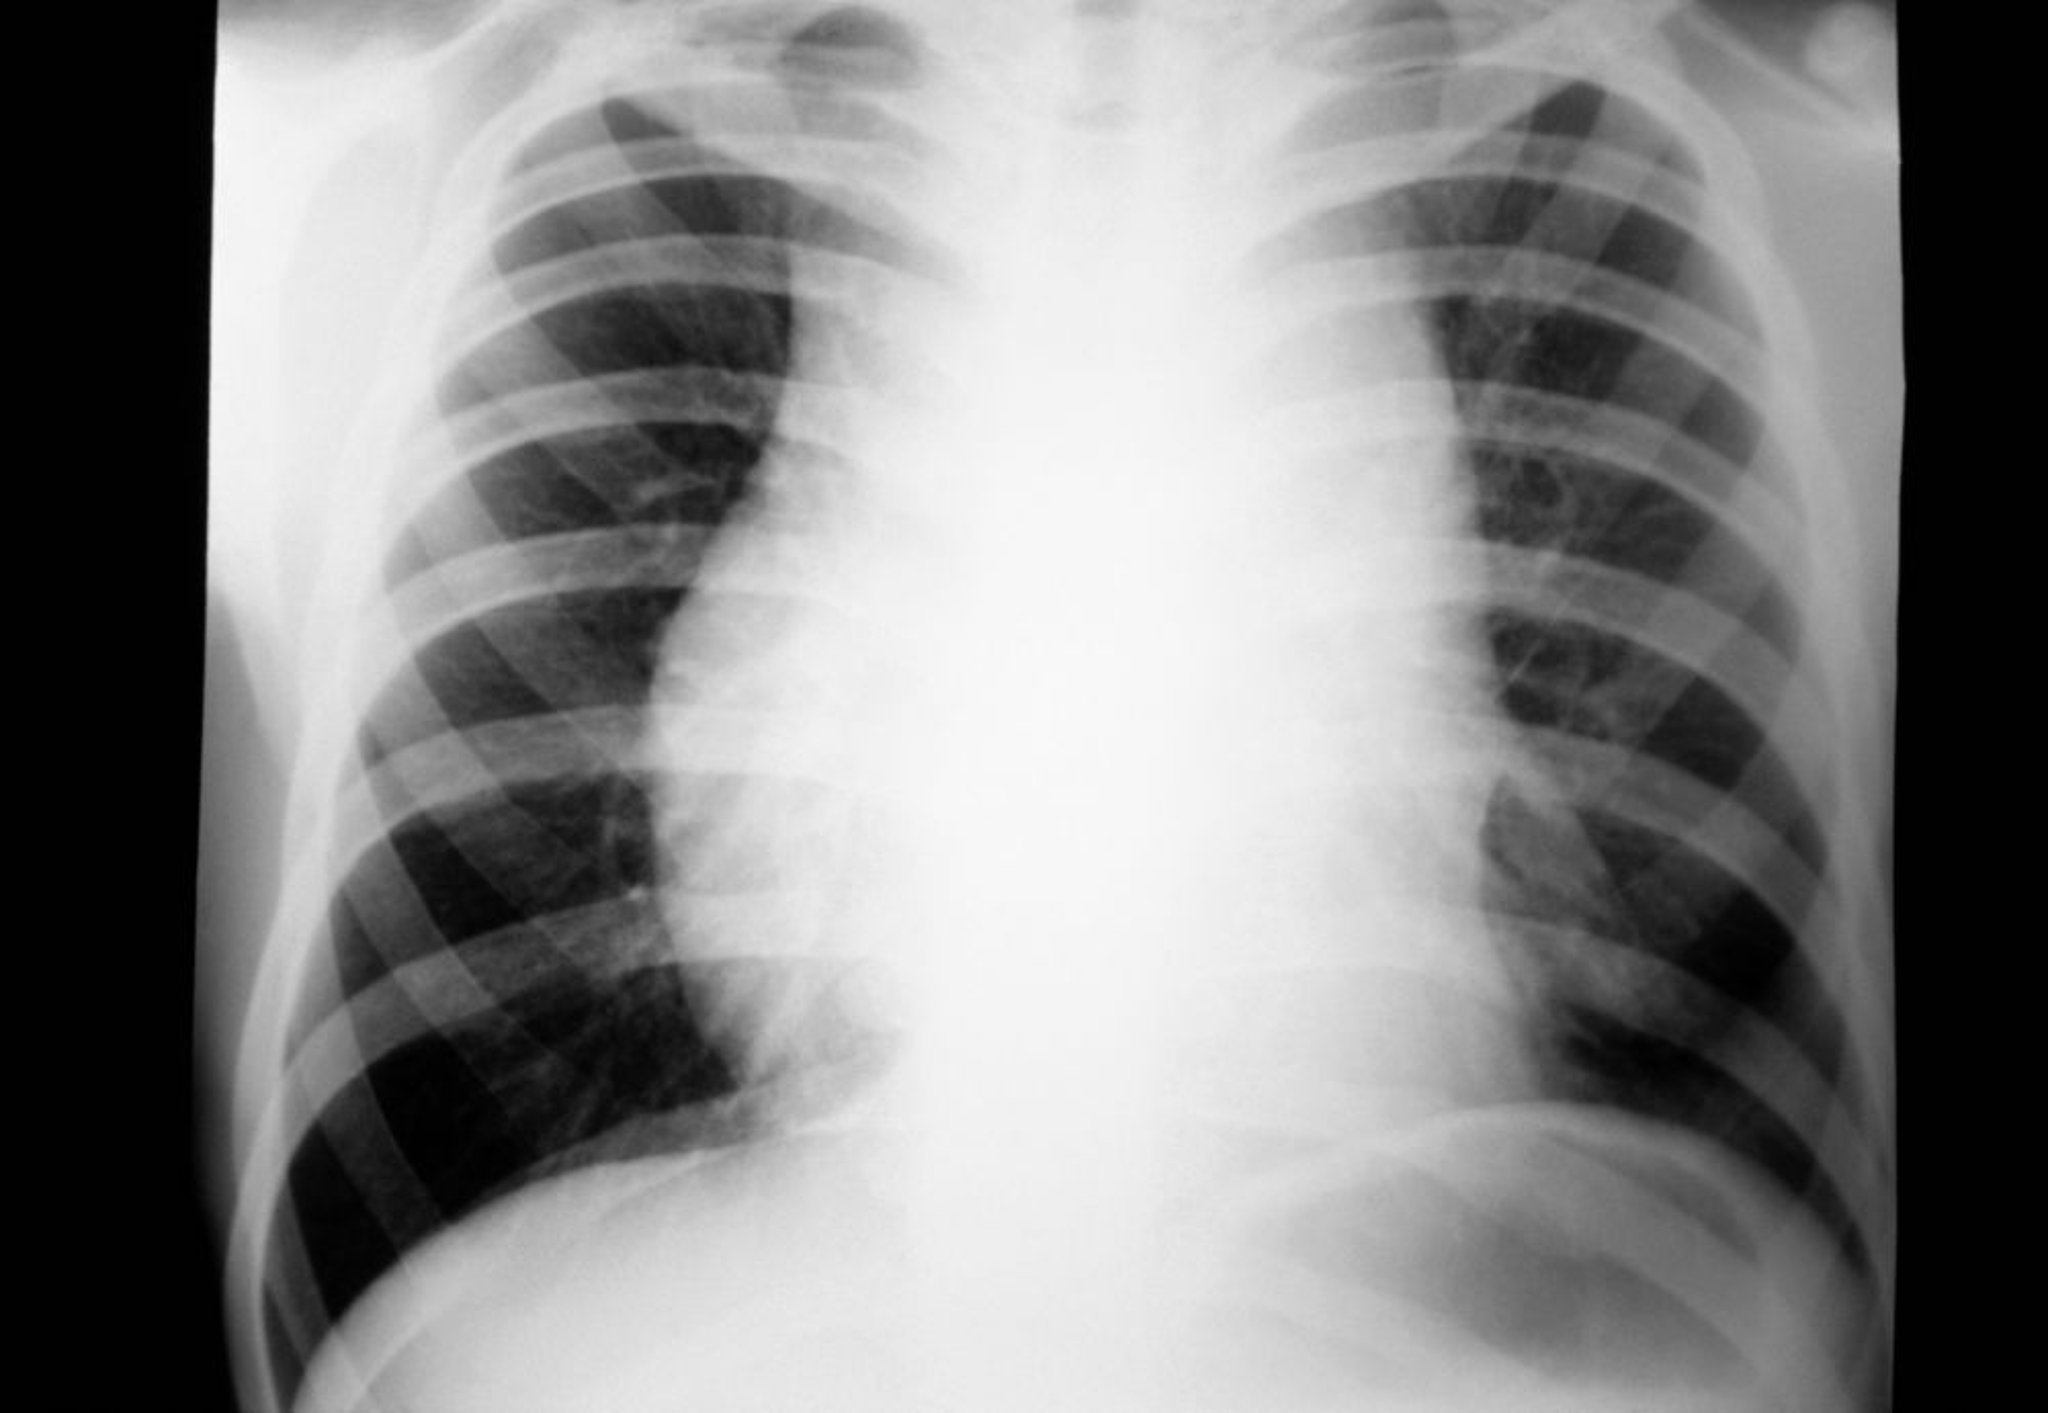

Лимфома Ходжкина (медиастинальная лимфаденопатия)

На рентгене грудной клетки пациента с лимфомой Ходжкина видна медиастинальная лимфаденопатия.